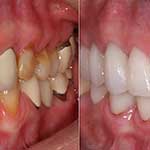

Η Αισθητική οδοντιατρική ασχολείται με παρεμβάσεις που έχουν ως στόχο τη βελτίωση της εμφάνισης των δοντιών και γενικότερα του στόματος, περιστατικά τα οποία δεν αντιμετωπίζουν τις περισσότερες φορές κάποιο ιατρικό πρόβλημα όμως ο ασθενής επιθυμεί την αισθητική παρέμβαση του οδοντιάτρου με στόχο την βελτίωση του χαμόγελου του.

Τα πιο συνηθισμένα προβλήματα που αντιμετωπίζει η αισθητική οδοντιατρική είναι:

Κίτρινα ή “λεκιασμένα” δόντια

Κενά ανάμεσα στα δόντια

Ορθοδοντικά προβλήματα

Μεταλλικά (μαύρα) σφραγίσματα

Σπασμένα / Ραγισμένα δόντια

Δόντια που λείπουν